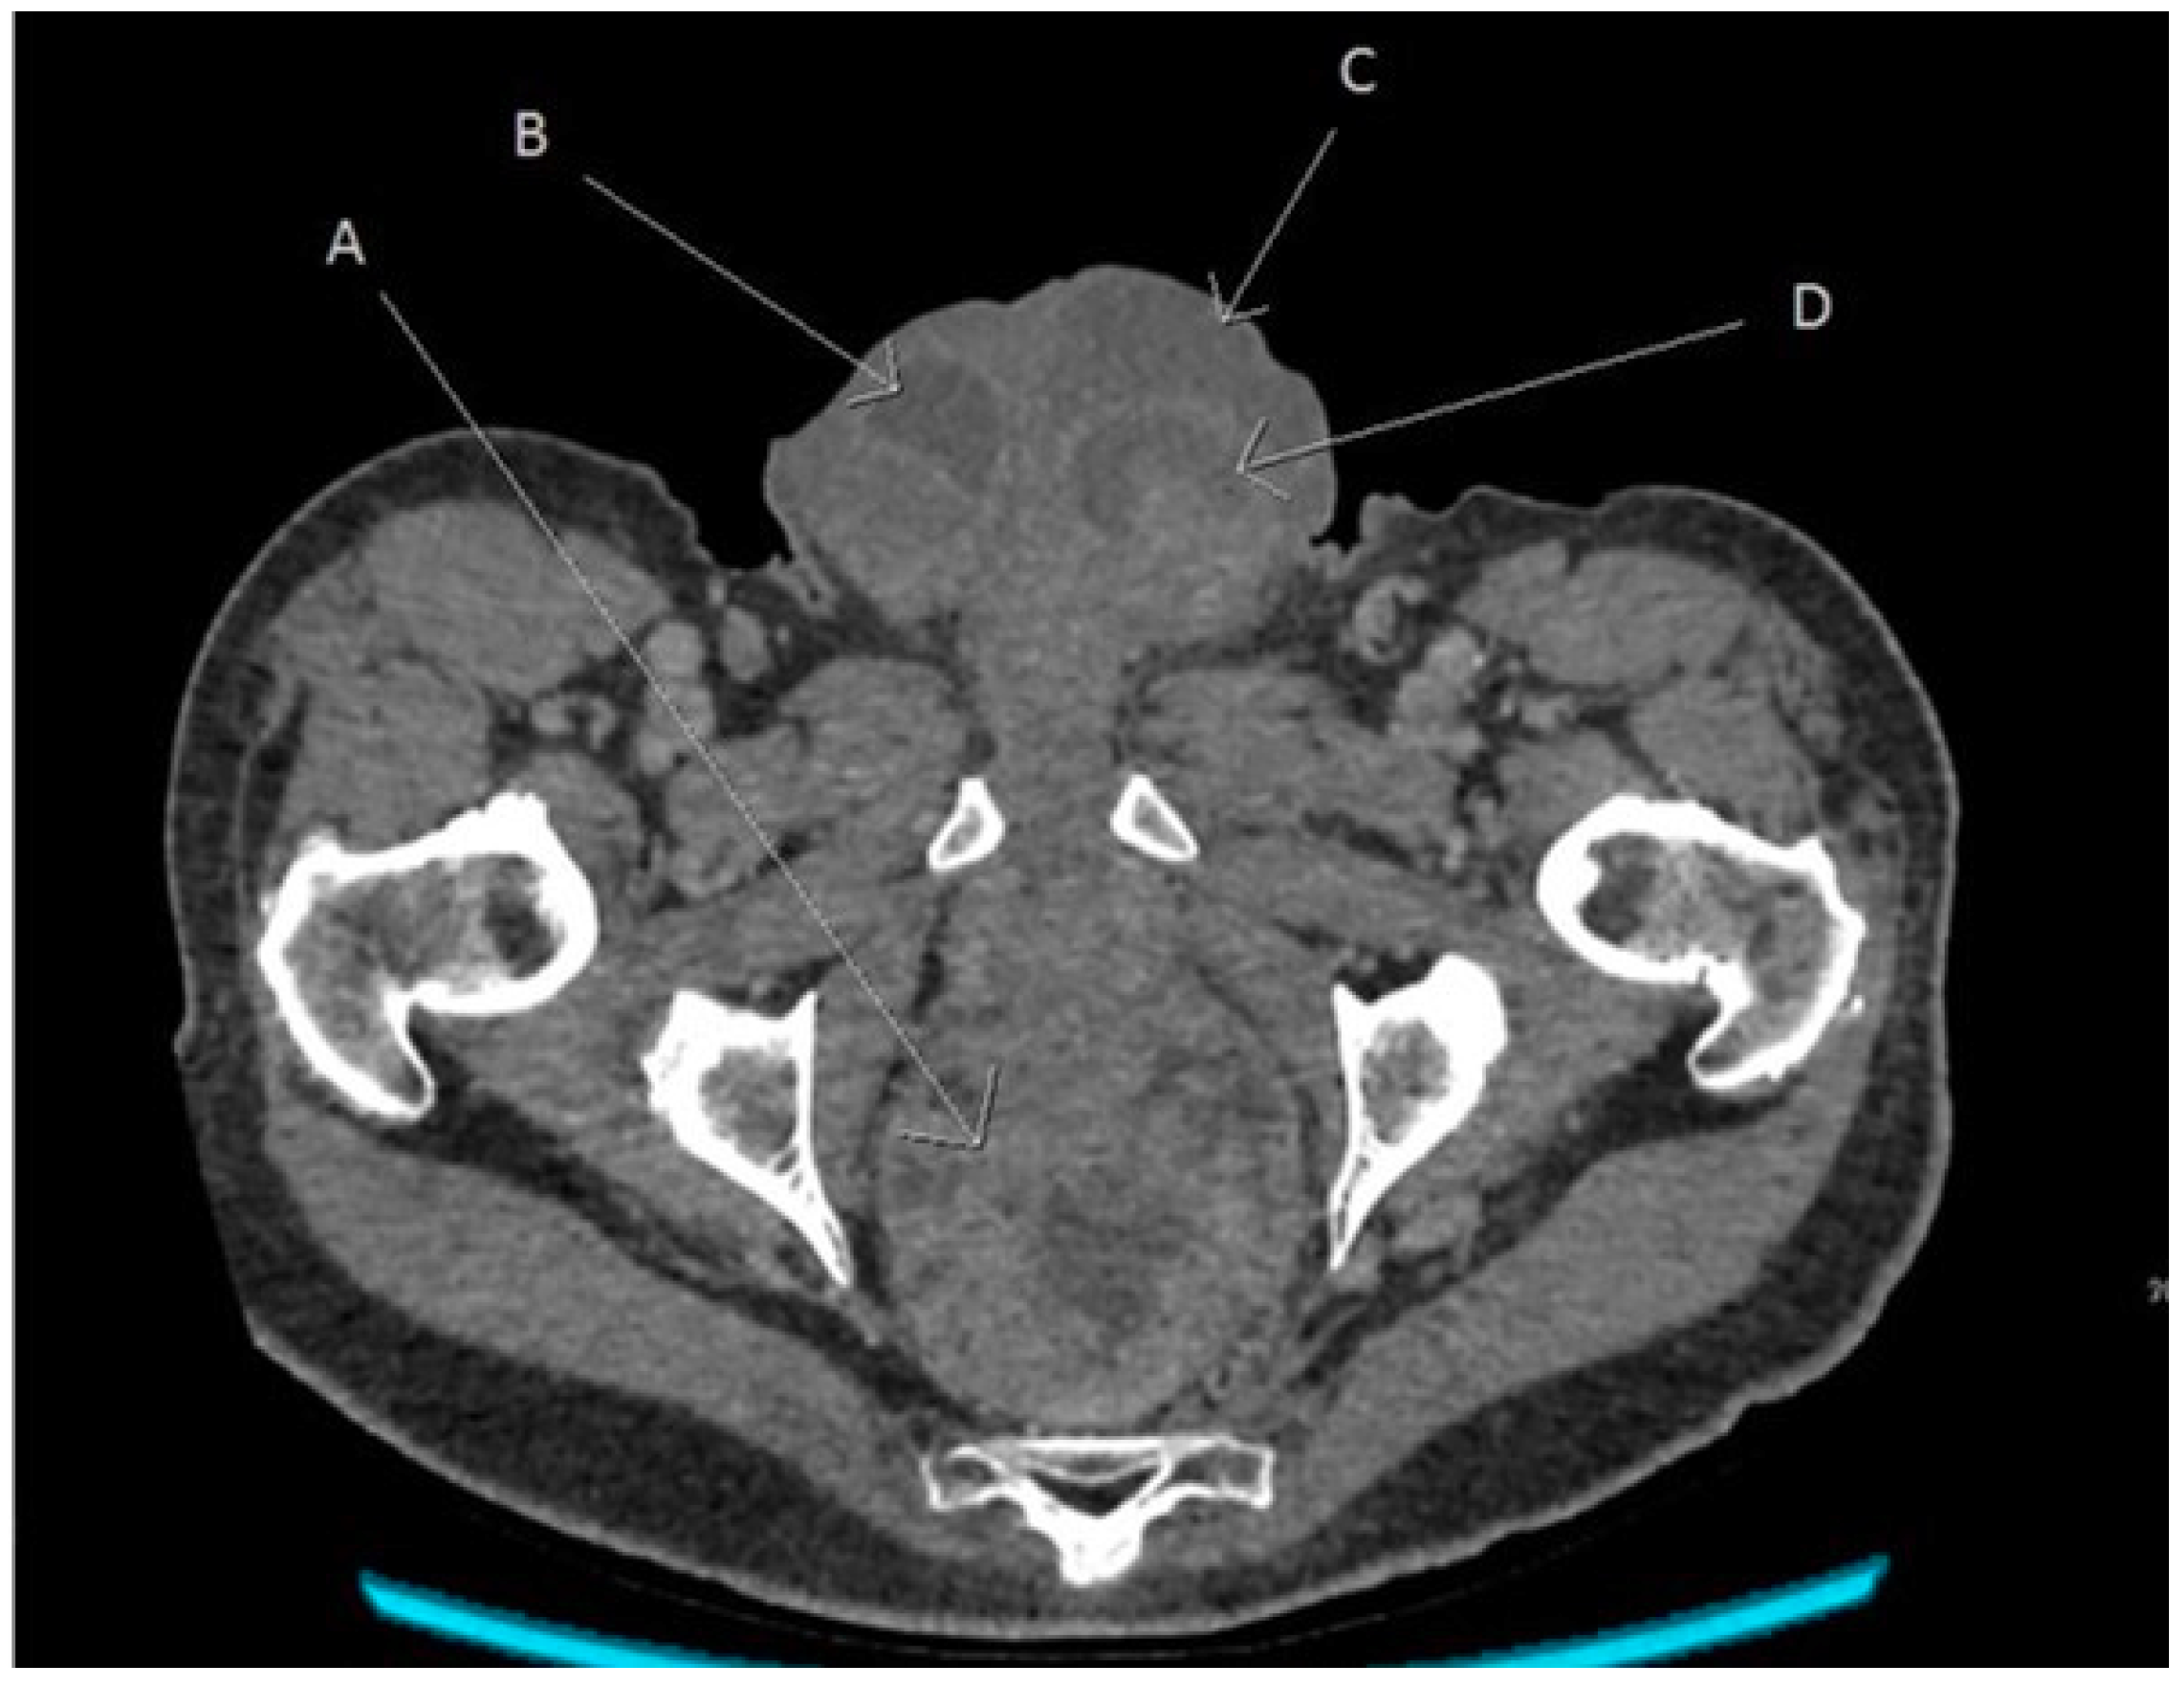

An urgent computed tomography scan was requested, revealing a possible rectal cancer with bilateral hydrocoeles (Figure 1). Urgent debridement of the scrotal tissue for Fournier’s gangrene was undertaken. Rectal biopsies revealed a villous adenoma with a high-grade dysplasia. The scrotal biopsies showed surface ulceration of the skin with a pronounced acute inflammatory infiltrate with abscess formation and infarction in the underlying dermis which extended to involve the subcutaneous tissues and adherent underlying testicular tissue and tracts along the epididymis in keeping with Fournier’s gangrene. Causative organisms were Staphylococcus aureus and Escherichia coli.

Figure 1. Angled axial reconstruction computed tomography image of abdomen and pelvis showing the rectal tumour, scrotal collection, and bilateral hydrocoeles. A—Rectal tumour, B—Right hydrocele, C—Left scrotal collection, and D—Left hydrocele.